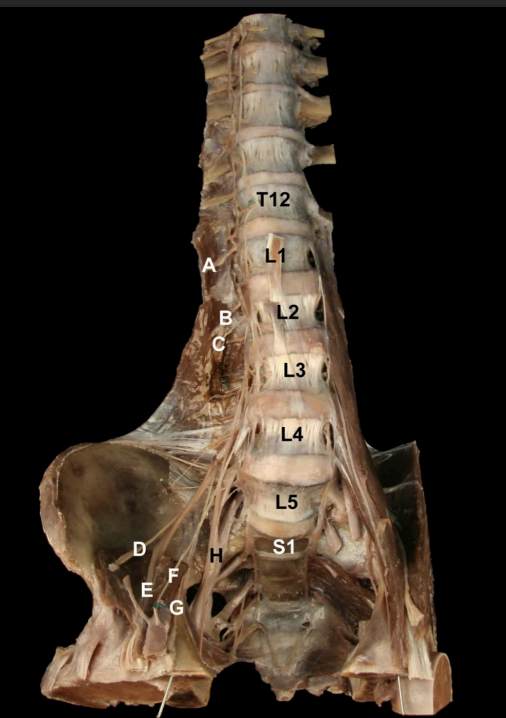

<p>Identify the Nerves and their corresponding nerve levels indicated on this <strong>Anterior view</strong> of the Pelvis:<strong> Lumbar Plexus</strong></p>

Identify the Nerves and their corresponding nerve levels indicated on this Anterior view of the Pelvis: Lumbar Plexus

A. Subcostal n (T12)

B: Iliophypogastric n (L1)

C: Ilioinguinal n, (L2)

D: Lateral Cutaneous n. of the Thigh (L2-L3)

E: Femoral n (L2-L4)

F: Genitofemoral n. (L1-L2)

G: Obturator n. (L2-L4)

H: Lumbosacral Trunk (L4-L5)